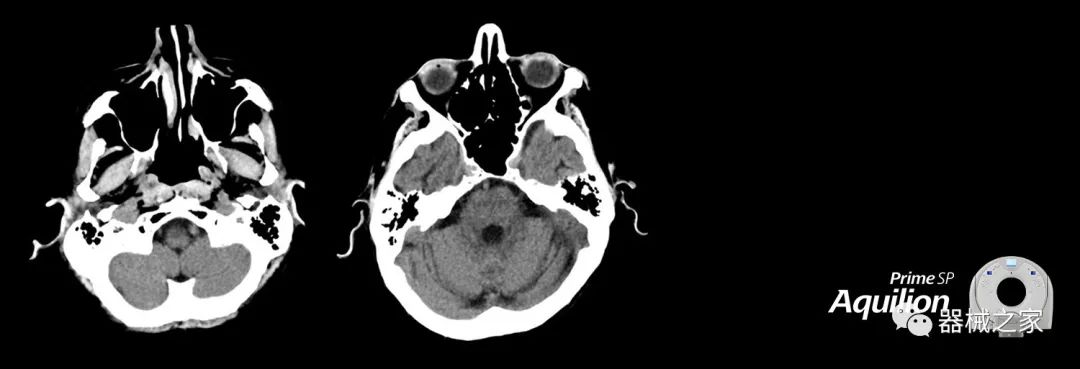

兩個CT系統(tǒng)均采用0.5 mm x 80排PUREViSION探測器技術(可配置并從80-160現(xiàn)場升級),78 cm孔徑,50 cm視野,AIDR(自適應迭代劑量減少)3-D和SEMAR(單個)能量金屬神器減少)技術。

Aquilion Prime SP使設施能夠處理具有挑戰(zhàn)性的案例,同時為員工提供快速,靈活和高效的解決方案。

佳能醫(yī)療的Aquilion Lightning 80掃描儀還以緊湊,經濟的包裝提供高質量的成像。Aquilion Lightning 80旨在可靠,高效地運行,在繁忙的環(huán)境中生成高質量的圖像。